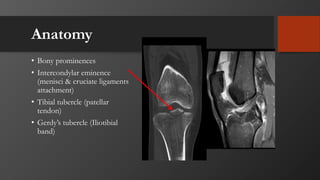

Anatomy

• Bony prominences

• Intercondylar eminence

(menisci & cruciate ligaments

attachment)

• Tibial tubercle (patellar

tendon)

• Gerdy’s tubercle (Iliotibial

band)